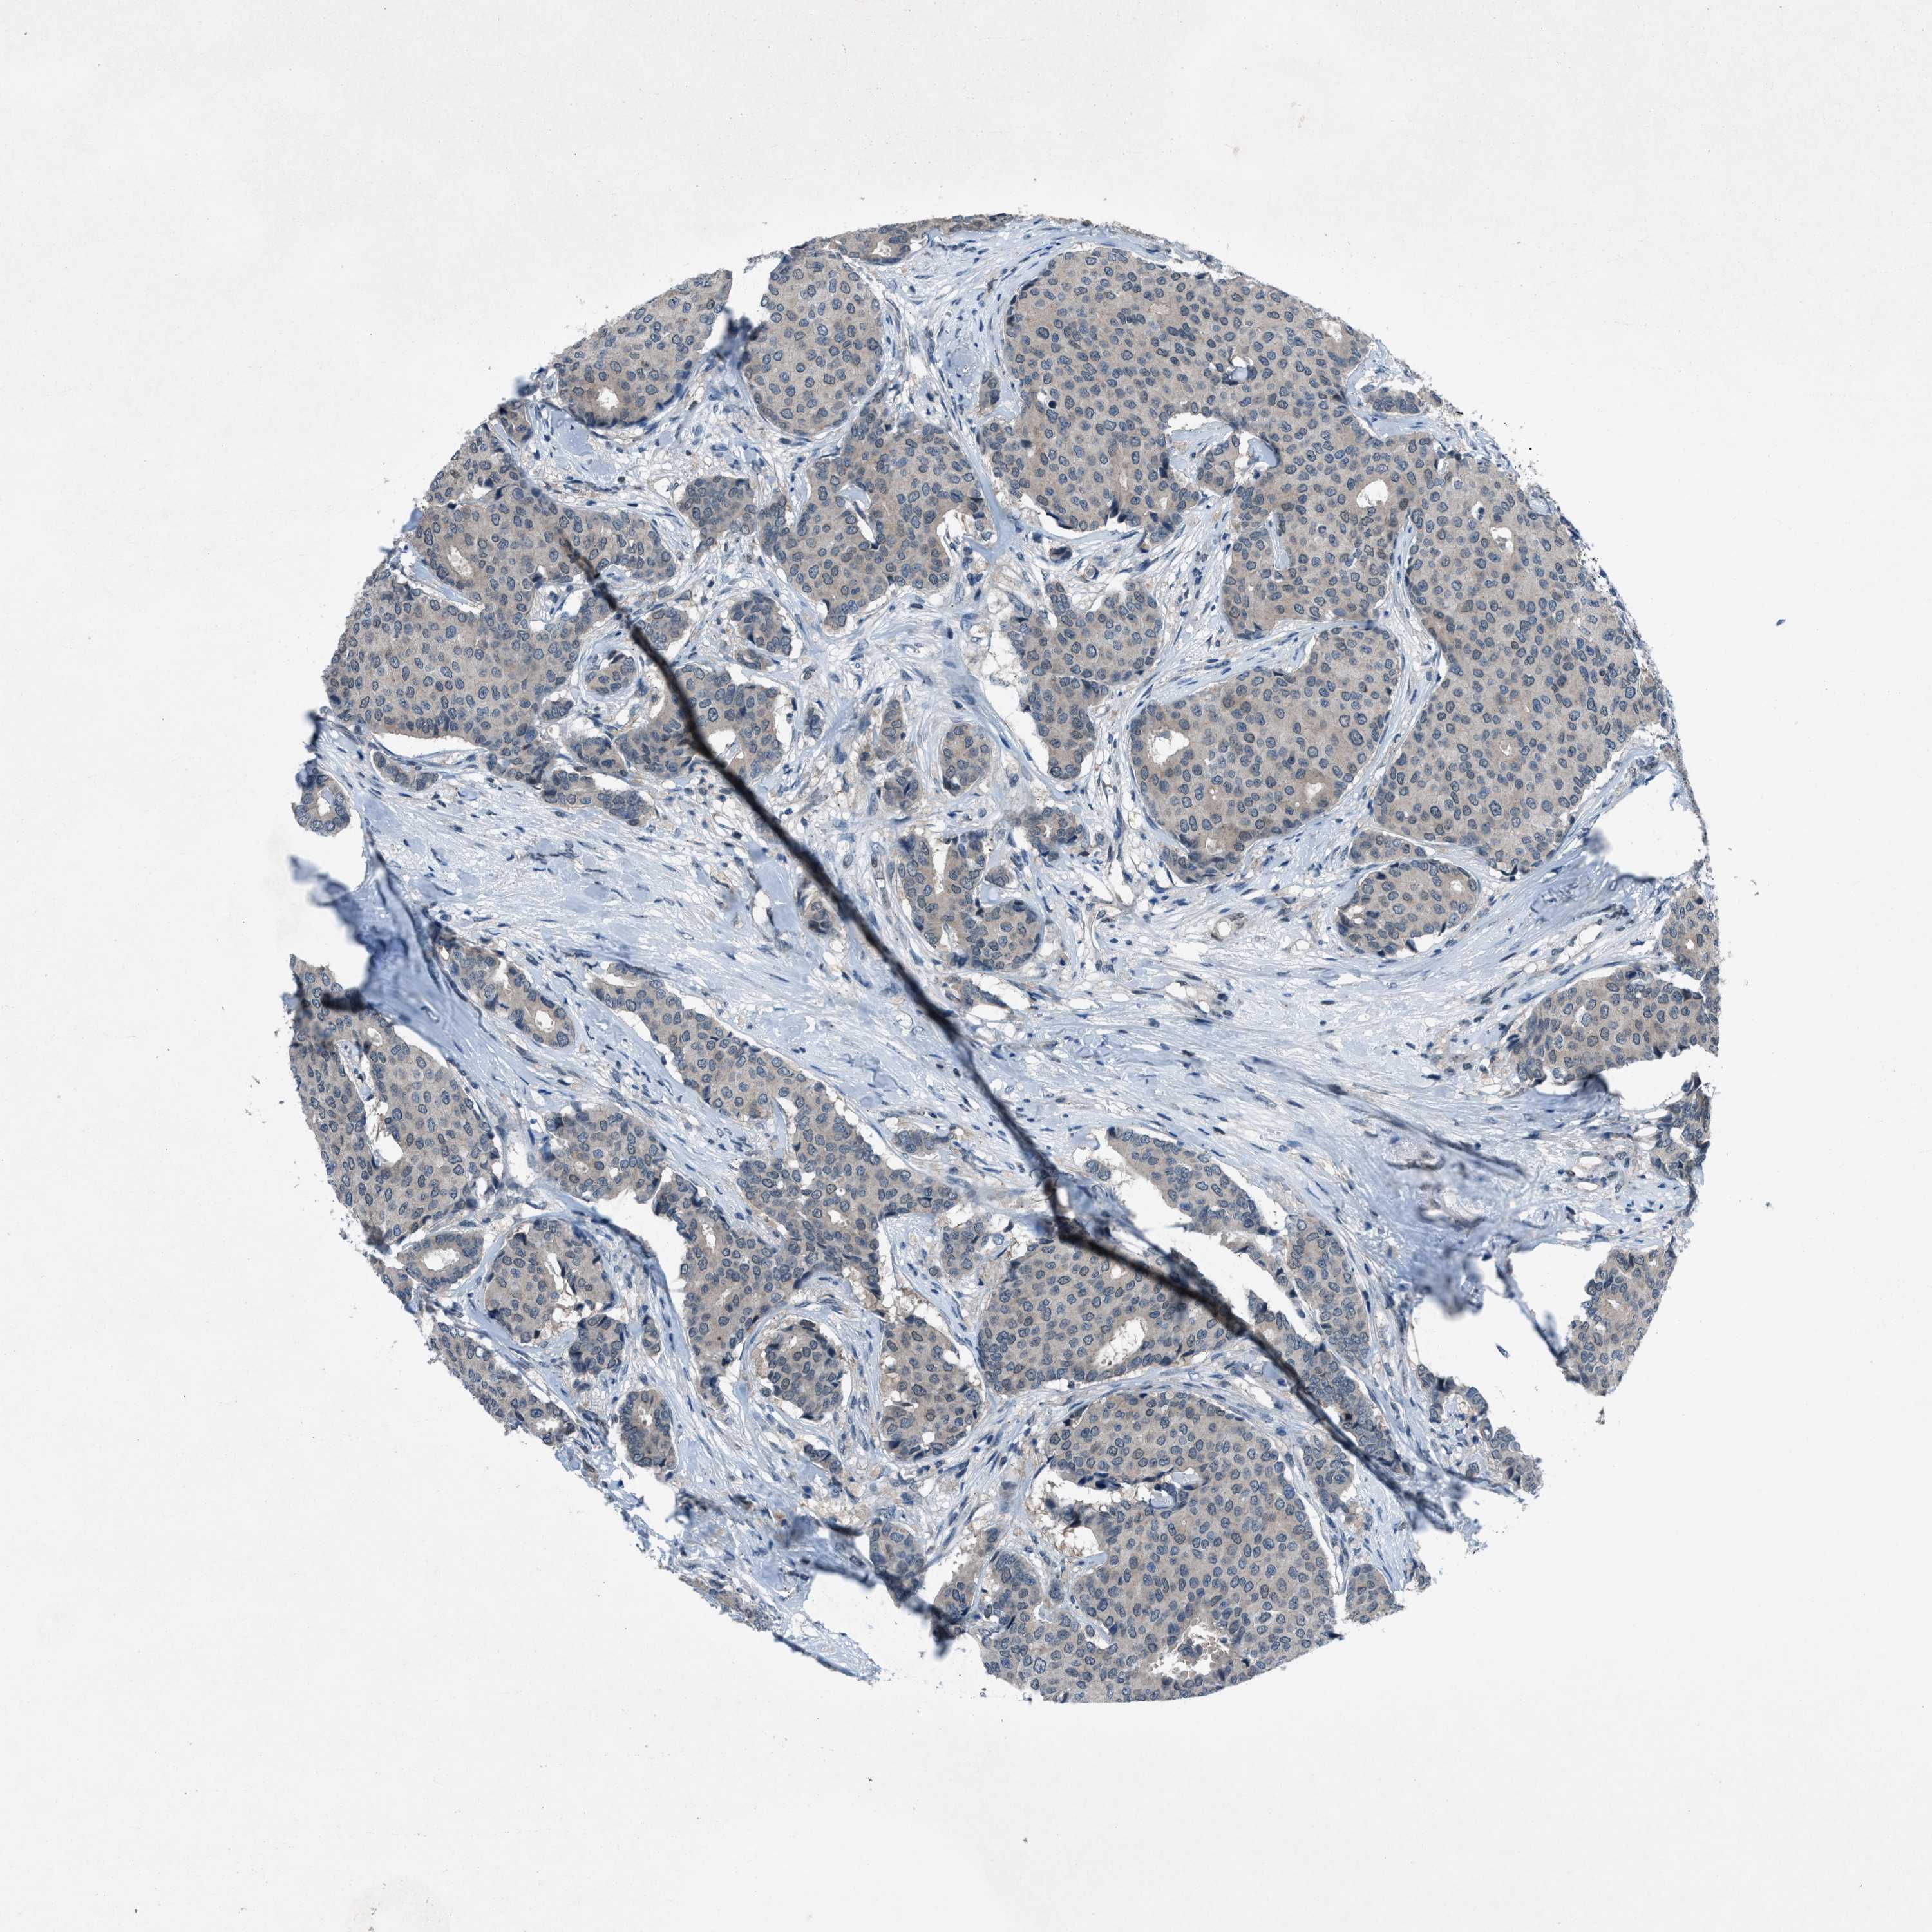

CANCER BREAST CANCER Show tissue menu

BRCA TCGA BRCA VALIDATION PROTEIN EXPRESSION

Breast cancer

Human cancer